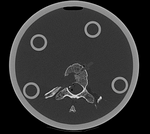

this is the fixed reference image. All images are aligned into this space lleft this is the moving image. The transform is calculated by matching this to the reference image

fixed image/target moving image

We have 2 in vitro CT scans of a human thoracic spine, before and after application of a controlled structural damage. We apply a rigid registration to bring the two images into alignment. Because the container tube and fixtures add image content that is "distracting" to the registration, we crop both images to contain just the vertebra of interest. Also the spines were not imaged in the same orientation, and as consequence we have an inverted z-axis in one of the images we have to correct first. Finally the two images have very different spatial origins (as defined in original DICOM header), so we need to recenter first before running the registration.

RegLib C39 registered.gif after rigid alignment. (click to enlarge)